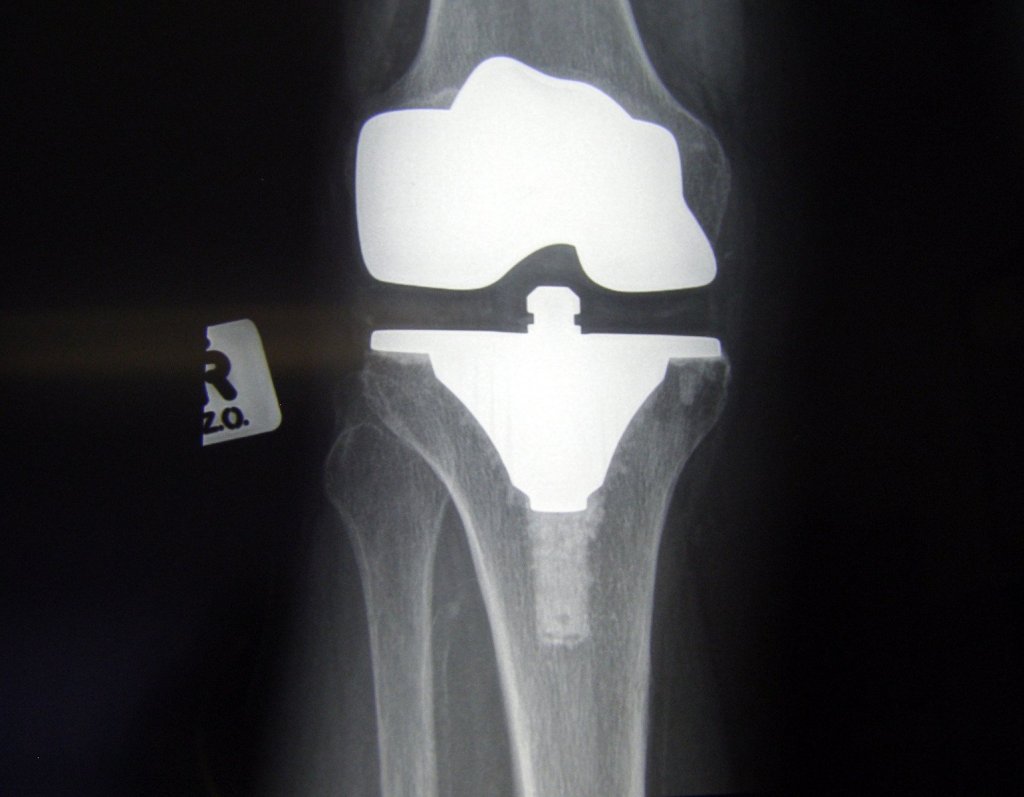

So it’s been four weeks since my knee was replaced and I’ve yet to go stir crazy. I have read, I have walked. I was in the CPM machine for two hours at a time 2-3 times a day. I slept. I iced. I medicated. I have done stretches and exercises and tried to be as independently functioning as possible.